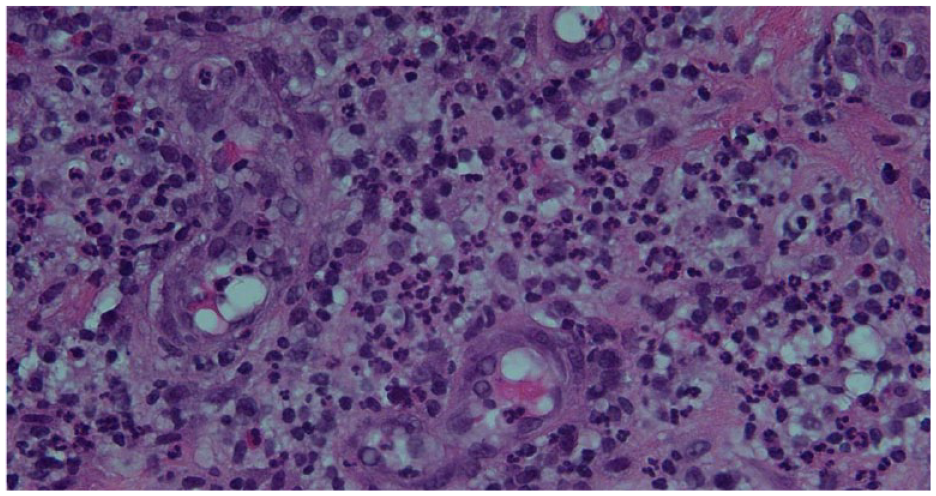

Mammography and breast ultrasound revealed a 7-cm nodular and irregular area involving the right breast at 8 o’clock (Figure 1A and B). In addition, there was a suspicious right axillary lymph node 21 mm (Figure 1 C and D). However, no abnormalities were detected in the left breast. Biopsy of the breast mass showed widespread acute inflammation, abscess formation, and fat necrosis (Figure 2).

Acute inflammation consisting of neutrophils with prominent vessels. Scattered eosinophils and lymphocytes are also seen. (Hematoxylin and Eosin stain, original magnification 40×).